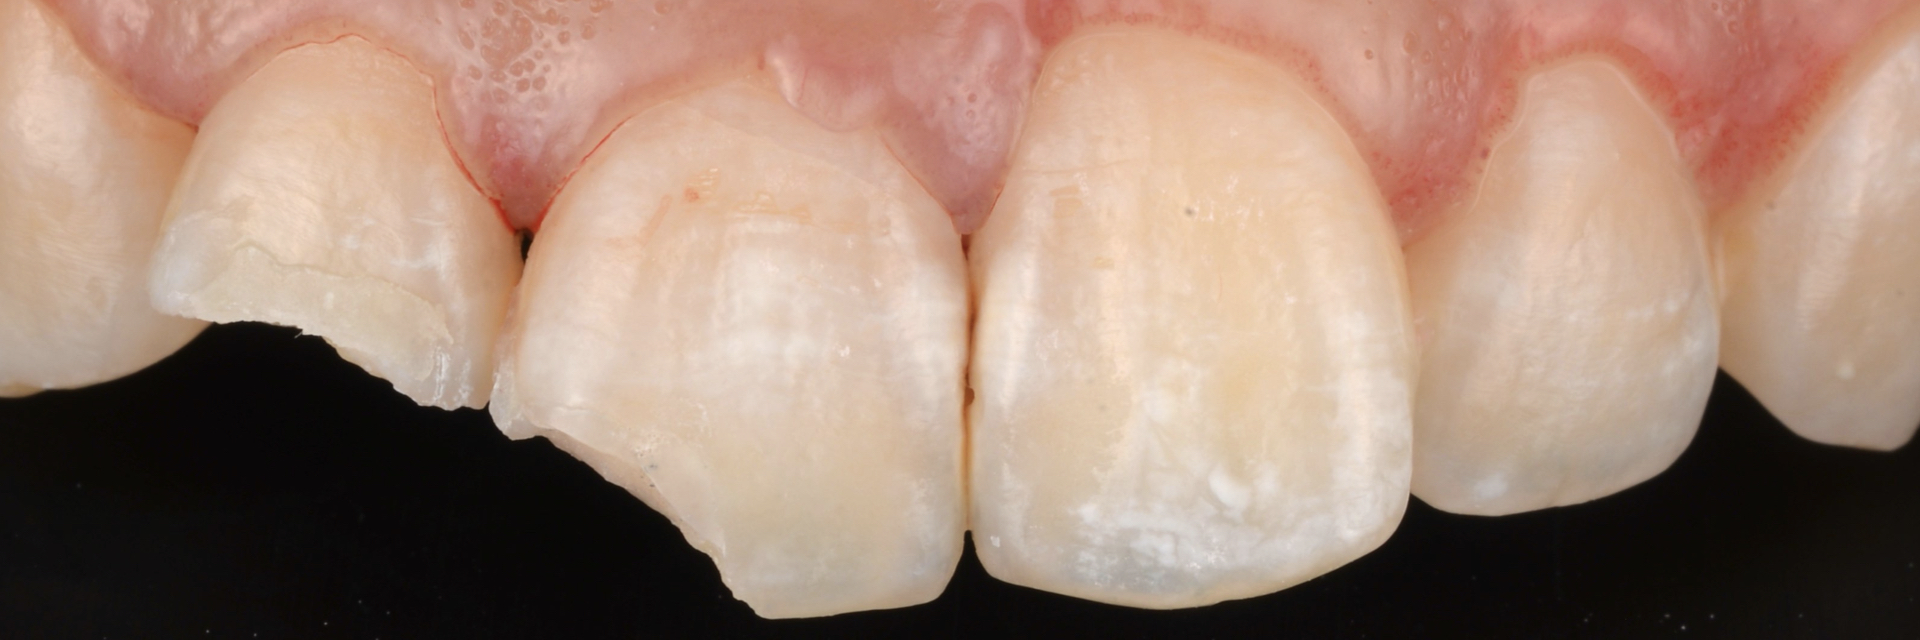

治療前